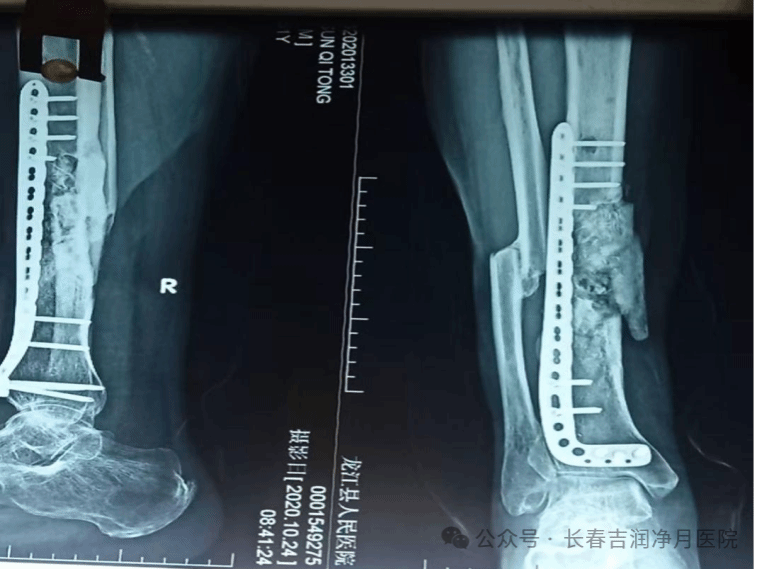

2019年5月,56岁的张先生因高空坠落钢管致右胫腓骨严重开放性骨折,在外院接受了包括清创外固定、骨水泥占位、内固定植骨及皮瓣修复在内的多次手术治疗。然而,复杂创伤的后续反应在2021年显现——张先生右小腿出现创口破溃、流脓,被诊断为“创伤后慢性骨髓炎”。于铁成主任团队接诊后,为他进行了病灶清创、外固定架稳定及抗生素链珠置入术,有效控制了急性感染。

(2020年10月,外院做完手术的右胫腓骨正侧位复查片)